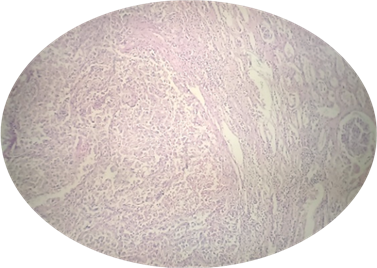

El estudio anatomopatológico demuestra un carcinoma renal de células claras, Furhman 2 (figura 8) tumor renal de 12 cm dependiente del polo renal inferior y región interpolar, con involucro del seno renal (figura 9) y trombo tumoral sin afección al endotelio vascular (figura 10).